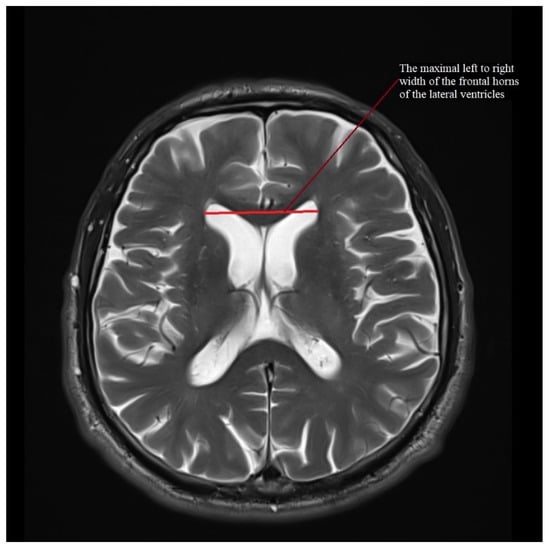

| MRPI | 11.247 (7.758–15.429) | 1.882 ± 1.39–2.912 | 17.384 (12.025–26.626) | 4.439 ± 3.183–7.327 | 19.366 (9.343–31.303) | 6.944 ± 5.247–10.27 | 10.766 (7.163–17.151) | 2.503 ± 1.915–3.614 | 15.363 (6.582–29.025) | 5.03 ± 3.801–7.439 |

| MRPI 2.0 | 2.342 (1.252–3.463) | 0.619 ± 0.457–0.958 | 4.338 (2.526–6.306) | 1.344 ± 0.964–2.219 | 5.646 (2.595–9.838) | 2.324 ± 1.756–3.436 | 2.558 (1.41–4.549) | 0.91 ± 0.696–1.314 | 4.195 (1.953–9.285) | 1.686 ± 1.274–2.493 |

| MIDBRAIN (cm2) | PSP-P vs. MSA-P | 0.85 | 0.93 | 0.846–1.0 | 0.0000 | 0.846 | 0.905 | 0.882 | 0.846 | 0.905 |

| M/P ratio | 0.177 | 0.934 | 0.856–1.0 | 0.0000 | 0.846 | 0.905 | 0.882 | 0.846 | 0.905 | |

| MRPI | 12.846 | 0.817 | 0.676–0.958 | 0.0000 | 0.923 | 0.619 | 0.735 | 0.6 | 0.929 | |

| MIDBRAIN (cm2) | PSP-P vs. Control | 1.03 | 0.938 | 0.849–1 | 0.0000 | 1 | 0.813 | 0.897 | 0.813 | 1 |

| M/P ratio | 0.202 | 0.995 | 0.98–1 | 0.0000 | 1 | 0.938 | 0.966 | 0.929 | 1 | |

| MRPI | 12.846 | 0.928 | 0.833–1 | 0.0000 | 0.923 | 0.875 | 0.897 | 0.857 | 0.933 | |

| MRPI 2.0 | 3.062 | 0.971 | 0.917–1 | 0.0000 | 1 | 0.875 | 0.931 | 0.867 | 1 |